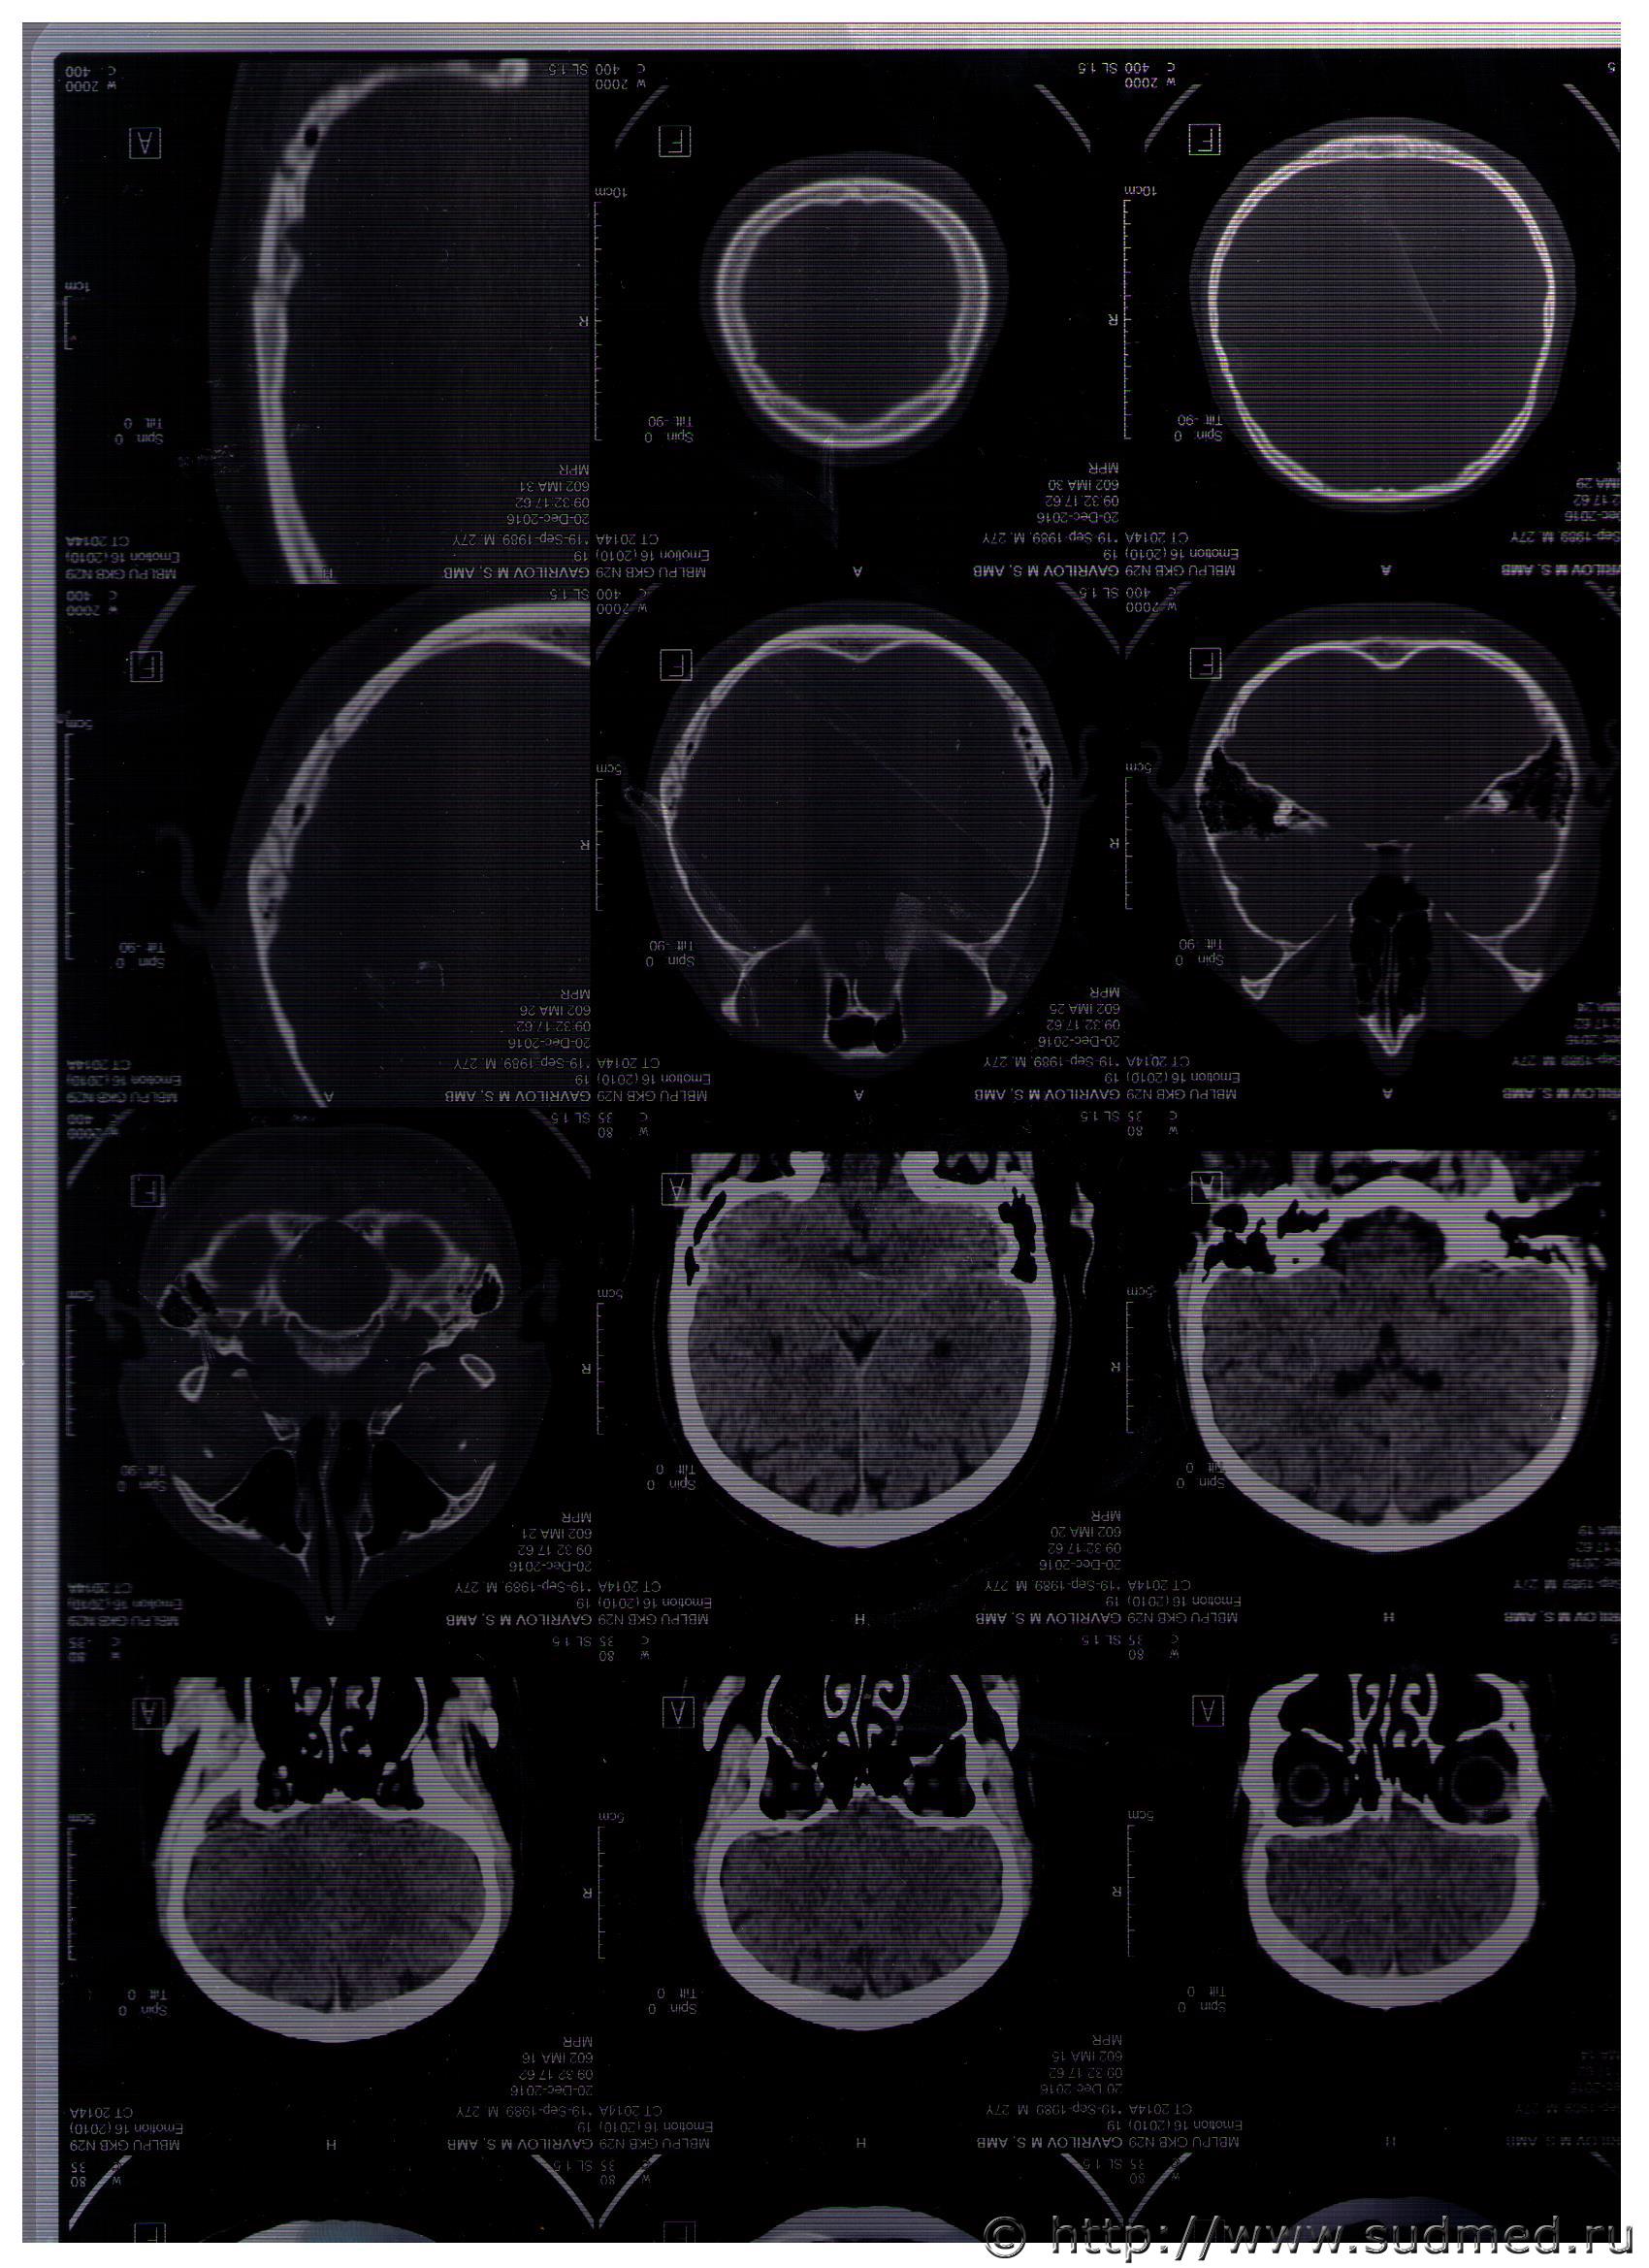

Уважаемые эксперты,я не врач.Однако рентгенолог описавший скт это и ещё 2 других которые я выкладывал лучший сосудистый хирург города,он и мрт расписывал одно из выложенных.

Из классики: швы свода черепа - наиболее прочные на разрыв части черепа. Отсюда правило - расхождение шва есть место приложения силы. Имеется переход расхождения в линейный перелом, то это происходит именно в этом порядке, т.е. расхождение шва переходит в перелом, но не наоборот.

Как у каждого порядочного правила имеются замечания и исключения:

1. Надо вести речь именно о расхождении шва, а не переломе по ходу шва.

2. Это правило применимо только к своду черепа

3. Есть одно исключение: линейный перелом затылочной кости может переходить в расхождение стреловидного шва, то тогда он будет входить в расхождение точно через вершину лямбды. Напротив: расходение стреловидного шва может переходить в перелом затылочной кости, но при этом никогда не переходит через вершину лямбды, а огибает ее и пересекая одну из ветвей лямбдовидного шва.

Это тогда что?Эксперт неопытный?)